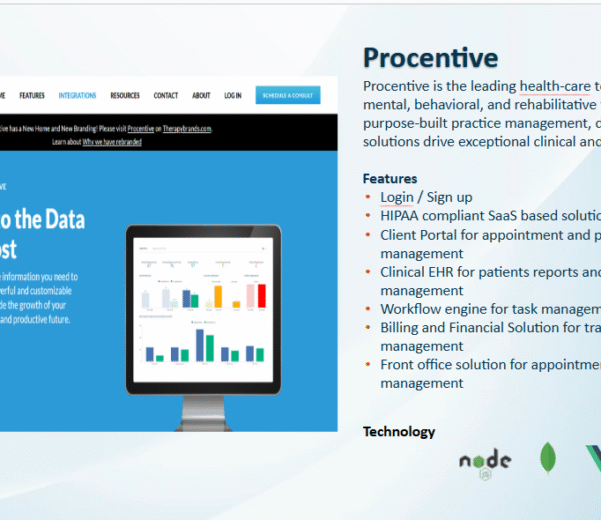

READ MORECase Study: Procentive – Empowering

Case Study: Procentive – Empowering Behavioral & Mental Health Management Through HIPAA-Compliant SaaS Problem Metric...

READ MORECase Study: Procentive – Empowering

Case Study: Procentive – Empowering Behavioral & Mental Health Management Through HIPAA-Compliant SaaS Problem Metric...